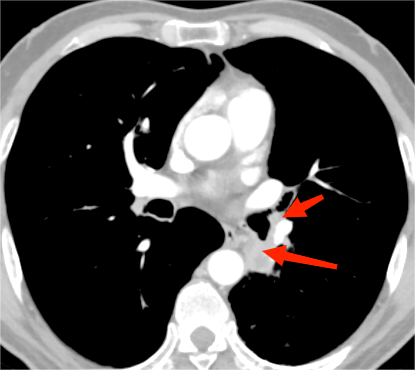

然而,肺功能和肿瘤位置差等因素对外科手术的挑战并没有消失!杨先生的肿瘤位于左肺下叶开口处,距离上下叶共同开口仅仅0.5厘米,并且肿瘤侵犯左侧肺动脉主干、下叶各动脉分支。这类患者往往需要进行左全肺切除或肺叶袖状切除,肺动脉成形,手术难度高,风险大。加上杨先生的肺功能根本无法耐受全肺切除,这给手术再次增加了难度。

杨先生的影像资料及诊断报告

为了保留杨先生的舌段肺功能,治疗团队采取了“雷霆手段”:阻断肺动脉主干及舌段动脉,切除受侵动脉壁,手工缝合肺动脉缺损;随后,切开下叶支气管根部,术中冰冻确定切缘无肿瘤残留后手工缝合封闭支气管残端。